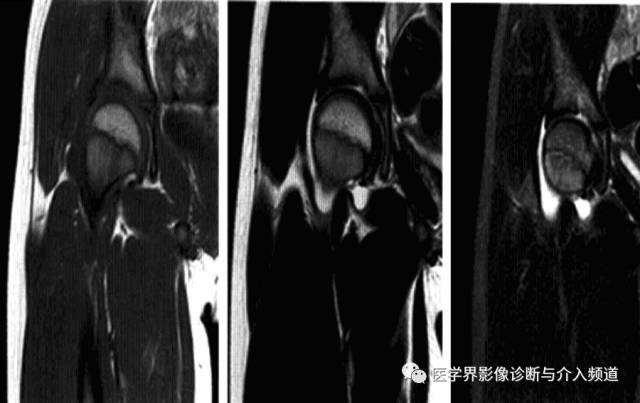

髋关节色素沉着绒毛结节性滑膜炎

一种侵及关节、腱鞘、滑囊或肌腱组织的良性增生伴色素沉着性病变。一般单关节发病,最常累及膝关节,其次是髋关节、踝关节、肩关节、肘关节。

病理:表面凹凸不平,有绒毛状滑膜皱襞覆盖,累及关节囊及周围软组织内血管和神经结构。

临床表现:以20-40岁青年女性多见,多有髋部外伤史,早期无特征,进展缓慢。

影像诊断:早期诊断缺泛特异性,晚期出现典型骨质破坏。MRI检查具较强特异性及定性诊断作用。